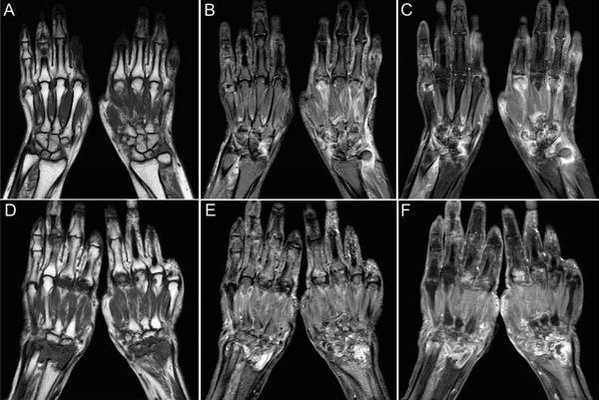

Первая из серии отобранных Т1 МР-томограмм левой кисти в аксиальной проекции. Обратите внимание на локтевые артерию и нерв в канале Гийона, а также на пульсирующий артефакт (двоение) от лучевой артерии на латеральной поверхности тыла запястья: Этот артефакт в некоторых случаях помогает выявить нормальные сосудистые структуры. Аксиальная МР-томограмма левой кисти на уровне крючка крючковидной кости. Обратите внимание, что мышцы тенара начинаются от удерживателя сгибателей. На уровне крючка крючковидной кости локтевая артерия обычно проходит кпереди или с передне-медиальной стороны от крючка, тогда как локтевой нерв и его ветви обычно огибают крючок с латеральной стороны. Первая из серии отобранных Т1 МР-томограмм правой кисти в аксиальной проекции. Обратите внимание на локтевые артерию и нерв в канале Гийона, а также на пульсирующий артефакт (двоение) от лучевой артерии на латеральной поверхности тыла запястья. Этот артефакт в некоторых случаях помогает выявить нормальные сосудистые структуры. Аксиальная МР-томограмма правой кисти на уровне крючка крючковидной кости. Обратите внимание, что мышцы тенара начинаются от удерживателя сгибателей. На уровне крючка крючковидной кости локтевая артерия обычно проходит кпереди или с передне-медиальной стороны от крючка, тогда как локтевой нерв и его ветви обычно огибают крючок с латеральной стороны. Аксиальная Т1 МР-томограмма левой кисти, полученная через основания пястных костей. Длинная ладонная мышца прикрепляется к ладонному апоневрозу (листок фасции кнаружи от удерживателя сгибателей) и имеет вид срединного утолщения ладонного апоневроза. Мышца практически не имеет функционального значения, поэтому ее длинное сухожилие часто используется в качестве трансплантата при восстановлении других сухожилий. Аксиальная Т1 МР-томограмма левой кисти, полученная через середины пястных костей. На этом уровне мы находимся за пределами запястного канала. На срезе начинают появляться червеобразные мышцы, прилежащие к сухожилиям сгибателей. Аксиальная Т1 МР-томограмма правой кисти, полученная через основания пястных костей. Длинная ладонная мышца прикрепляется к ладонному апоневрозу (листок фасции кнаружи отудерживателя сгибателей) и имеет вид срединного утолщения ладонного апоневроза. Мышца практически не имеет функционального значения, поэтому ее длинное сухожилие часто используется в качестве трансплантата при восстановлении других сухожилий. Аксиальная Т1 МР-томограмма правой кисти, полученная через середины пястных костей. На этом уровне мы находимся за пределами запястного канала. На срезе начинают появляться червеобразные мышцы, прилежащие к сухожилиям сгибателей. На аксиальной Т1 МР-томограмме левой кисти показаны дистальные отделы тел пястных костей. Межсухожильные тяжи—это фиброзные пучки, соединяющие между собой сухожилия разгибателей II-V пальцев непосредственно проксимальнее пястно-фаланговых суставов. Эти фиброзные пучки предотвращают латеральное смещение сухожилий разгибателей над пястными костями. Вследствие наличия этих соединений, разгибание пальцев может оставаться относительно сохранным при полном разрыве одного из сухожилий общего разгибателя пальцев проксимальнее тяжа, и такое повреждение может не проявляться клинически. На аксиальной Т1 МР-томограмме левой кисти можно увидеть головку V пястной кости и дистальные отделы II-IV пястных костей. На аксиальной Т1 МР-томограмме правой кисти показаны дистальные отделы тел пястных костей. Межсухожильные тяжи—это фиброзные пучки, соединяющие между собой сухожилия разгибателей II-V пальцев непосредственно проксимальнее пястно-фаланговых суставов. Эти фиброзные пучки предотвращают латеральное смещение сухожилий разгибателей над пястными костями. Вследствие наличия этих соединений, разгибание пальцев может оставаться относительно сохранным при полном разрыве одного из сухожилий общего разгибателя пальцев проксимальнее тяжа, и такое повреждение может не проявляться клинически. На аксиальной Т1 МР-томограмме правой кисти можно увидеть головку V пястной кости и дистальные отделы II-IV пястных костей. На аксиальной Т1 МР-томограмме левой кисти все еще остаются видны головки II-IV пястных костей. Латеральные вырезки головок пястных костей служат местами начала коллатеральных связок, которые имеют сигнал промежуточной интенсивности и лежат под сагиттальными и латеральными пучками. Глубокие поперечные связки запястья соединяют ладонные пластинки II-V пальцев. На аксиальной Т1 МР-томограмме левой кисти показаны проксимальные фаланги. Латеральные пучки выявляются в виде латеральных утолщений сухожильного растяжения, а сухожилие общего разгибателя пальцев выглядит как центральное утолщение сухожильного растяжения. Поскольку срез получен проксимальнее проксимальных межфаланговых суставов, мы понимаем, что все еще находимся на уровне латеральных пучков, а не соединенных сухожилий. На аксиальной Т1 МР-томограмме правой кисти все еще остаются видны головки II-IV пястных костей. Латеральные вырезки головок пястных костей служат местами начала коллатеральных связок, которые имеют сигнал промежуточной интенсивности и лежат под сагиттальными и латеральными пучками. Глубокие поперечные связки запястья соединяют ладонные пластинки II-V пальцев. На аксиальной Т1 МР-томограмме правой кисти показаны проксимальные фаланги. Латеральные пучки выявляются в виде латеральных утолщений сухожильного растяжения, а сухожилие общего разгибателя пальцев выглядит как центральное утолщение сухожильного растяжения. Поскольку срез получен проксимальнее проксимальных межфаланговых суставов, мы понимаем, что все еще находимся на уровне латеральных пучков, а не соединенных сухожилий.